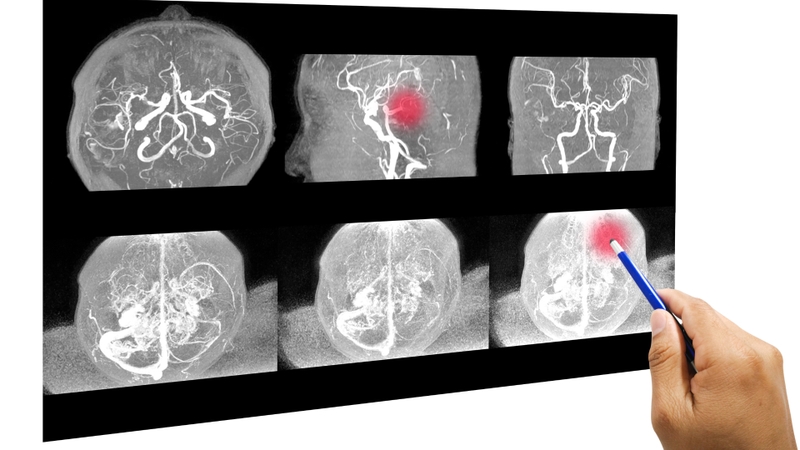

Xuất huyết não xảy ra khi máu tràn vào mô não và bắt đầu gây tổn thương cho não. Một khi máu đã tràn vào, tình trạng phù não sẽ xảy ra và bắt đầu hình thành các khối tụ máu. Điều này sẽ làm tăng áp lực lên các mô xung quanh, cuối cùng sẽ giết chết các tế bào não và vỡ mạch não.

Như đã đề cập ở trên, xuất huyết não là một tình trạng vô cùng nguy hiểm và có thể để lại nhiều biến chứng. Dưới đây là phương pháp chẩn đoán cũng như điều trị xuất huyết não mà bác sĩ có thể chỉ định cho bệnh nhân: